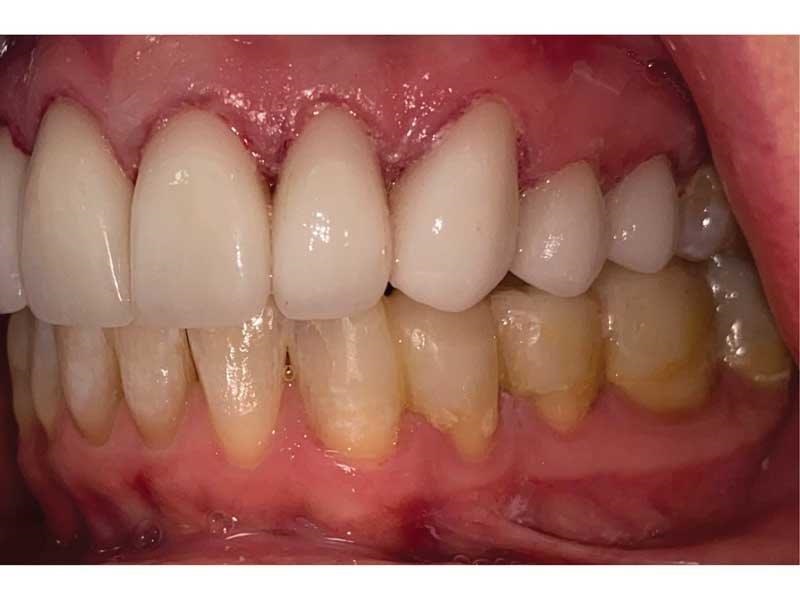

Meet Lorraine, who came into my office to “redo her bonding.” Lorraine had some upper anterior teeth done years ago with resin, which now was dull, stained and breaking down (Figs. 1–3). She had an amount of money in mind that she thought it would cost. She was very wrong.

Fig. 1

Fig. 2

Fig. 3